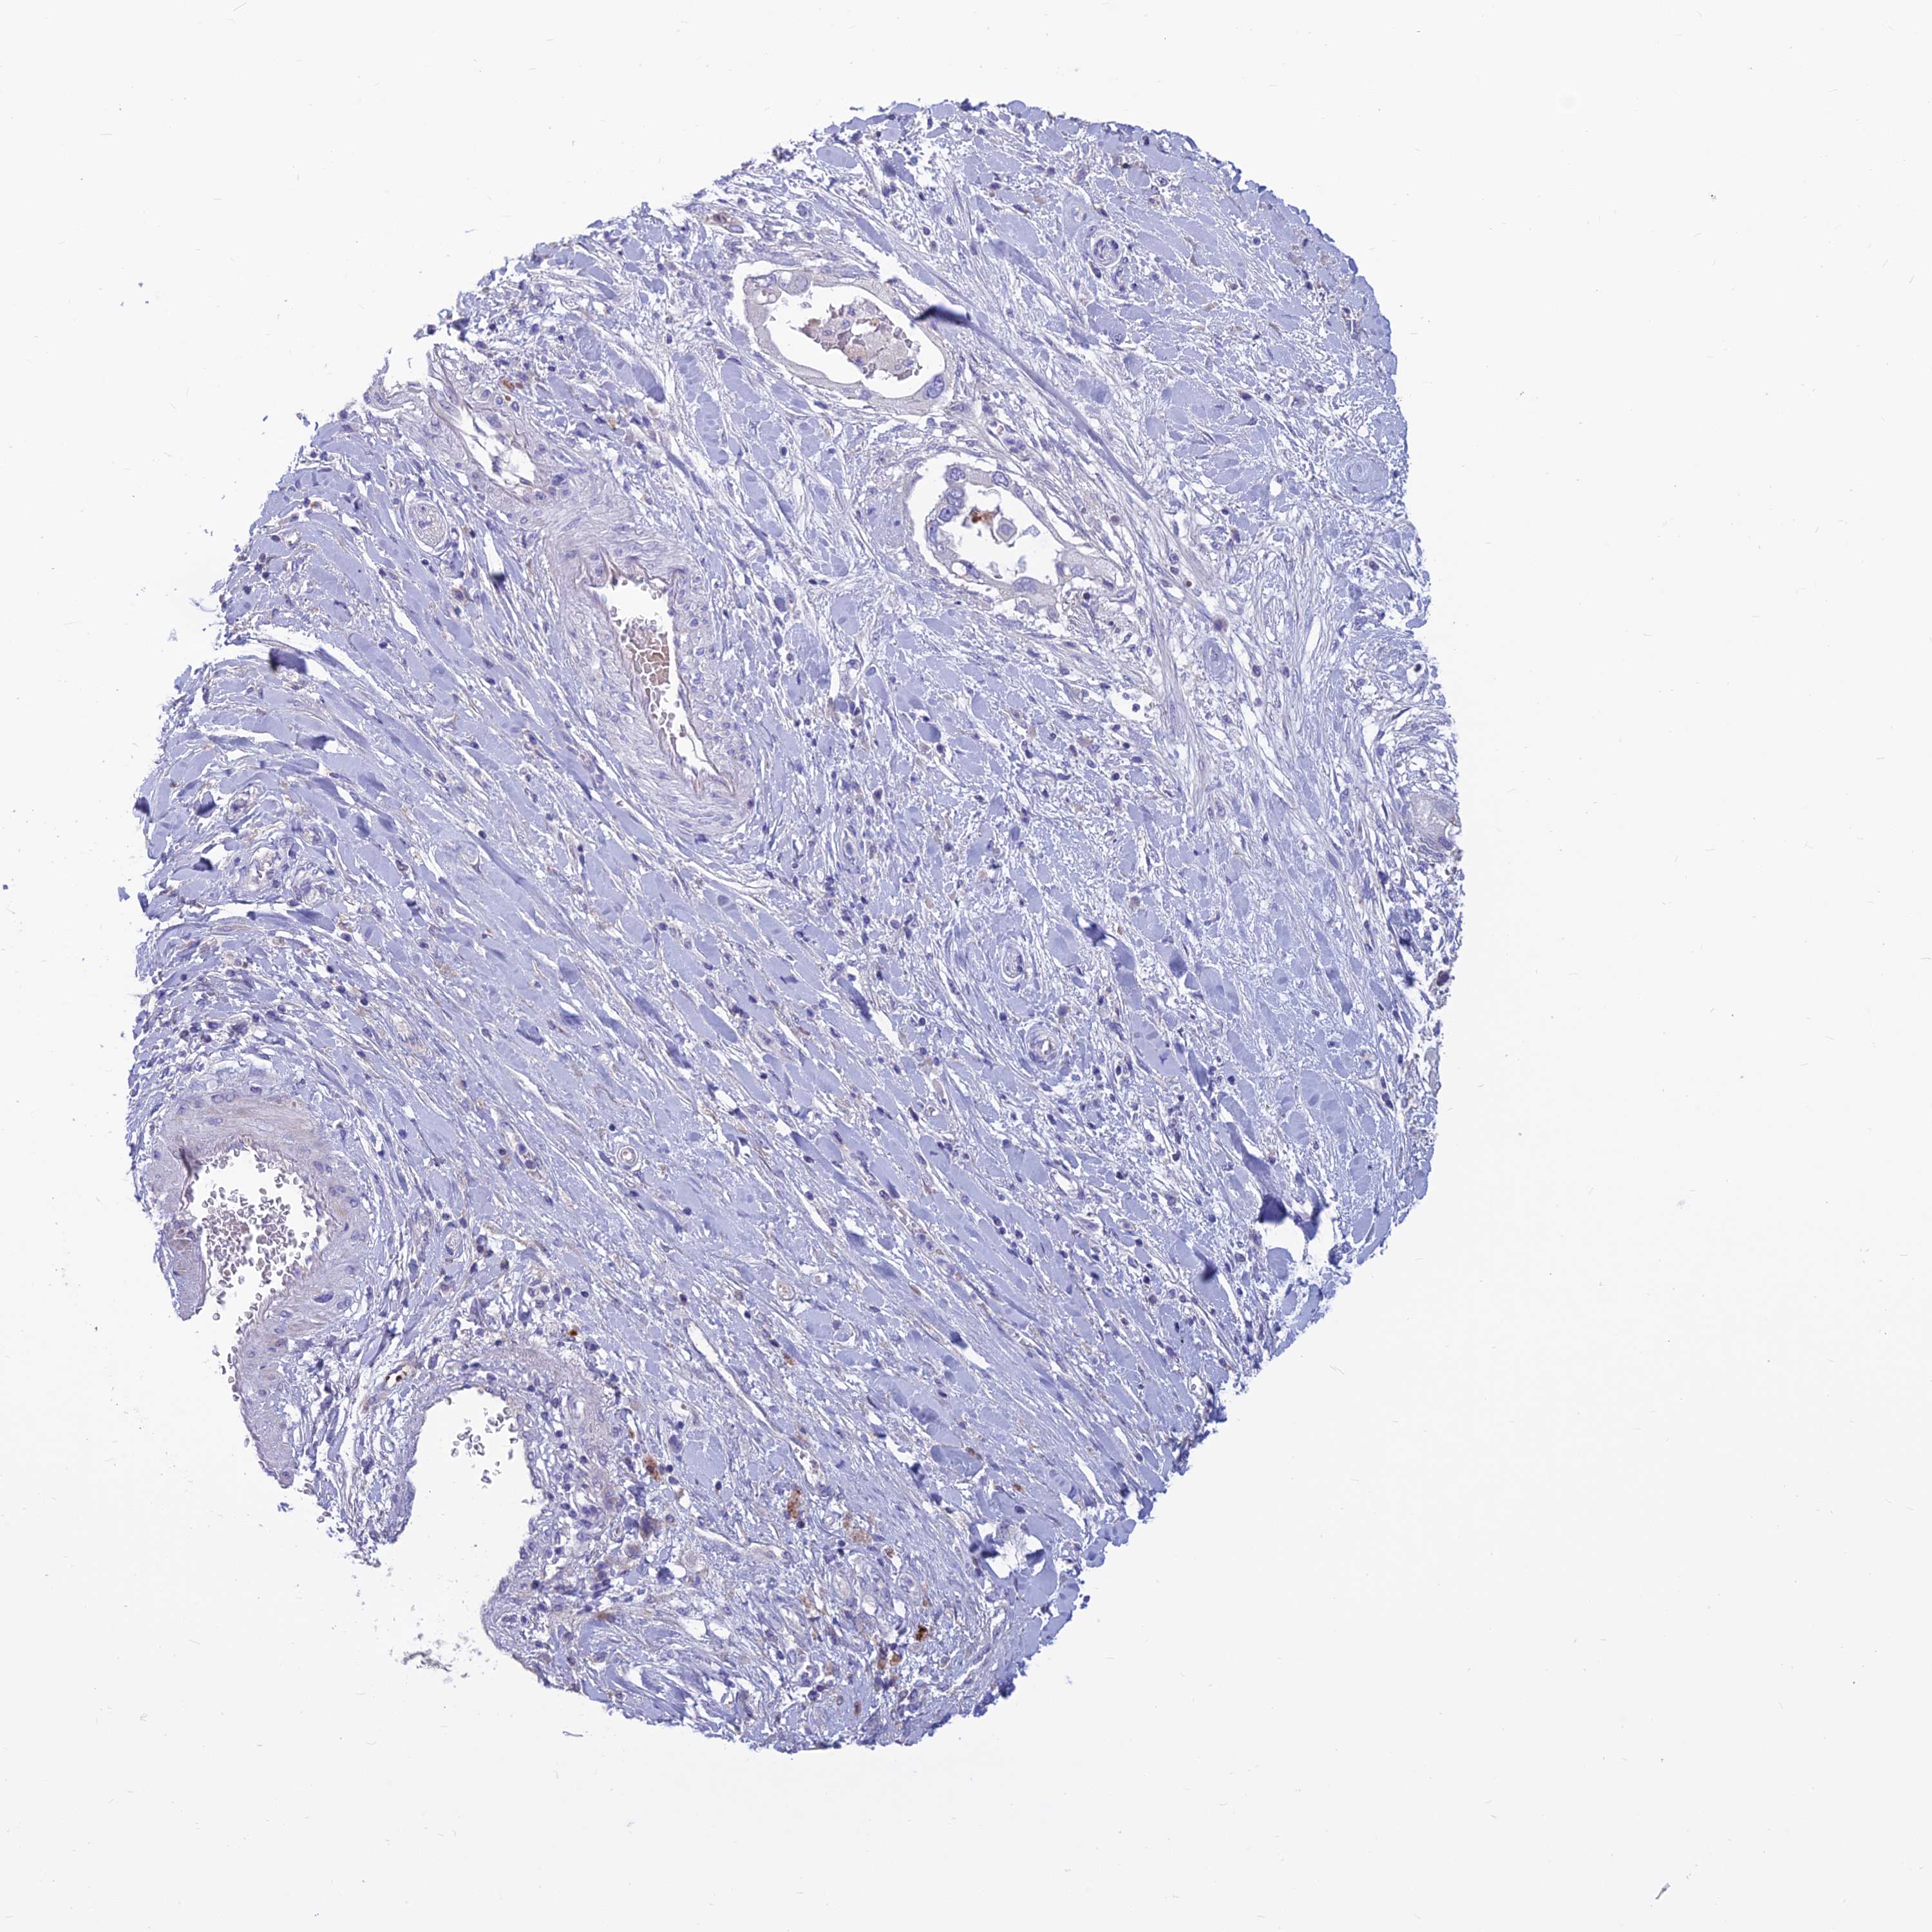

PANCREATIC CANCER - Protein expressioni

A mouse-over function shows sample information and annotation data. Click on an image to view it in a full screen mode. Samples can be filtered based on level of antibody staining by selecting one or several of the following categories: high, medium, low and not detected. The assay and annotation is described here.

Note that samples used for immunohistochemistry by the Human Protein Atlas do not correspond to samples in the TCGA dataset.

Antibody stainingi

Antibody staining in the annotated cell types in the current human tissue is reported as not detected, low, medium, or high, based on conventional immunohistochemistry profiling in selected tissues. This score is based on the combination of the staining intensity and fraction of stained cells.

Each image is clickable and will lead to virtual microscopy that enables deeper exploration of all samples and also displays staining intensity scores, fraction scores and subcellular localization as well as patient and tissue information for each sample.

Antibody HPA044573

Staining

High

Medium

Low

Not detected

Intensity

Strong

Moderate

Weak

Negative

Quantity

>75%

75%-25%

<25%

None

Location

Nuclear

Cytoplasmic/membranous

Cytoplasmic/membranous,nuclear

Adenocarcinoma, NOS